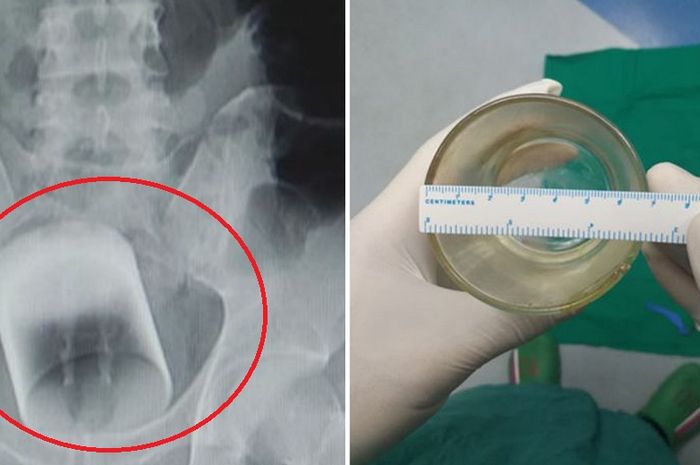

Alamak! Ada Gelas di Dalam Tubuh Pria ini, Kok bisa? - Semua ...